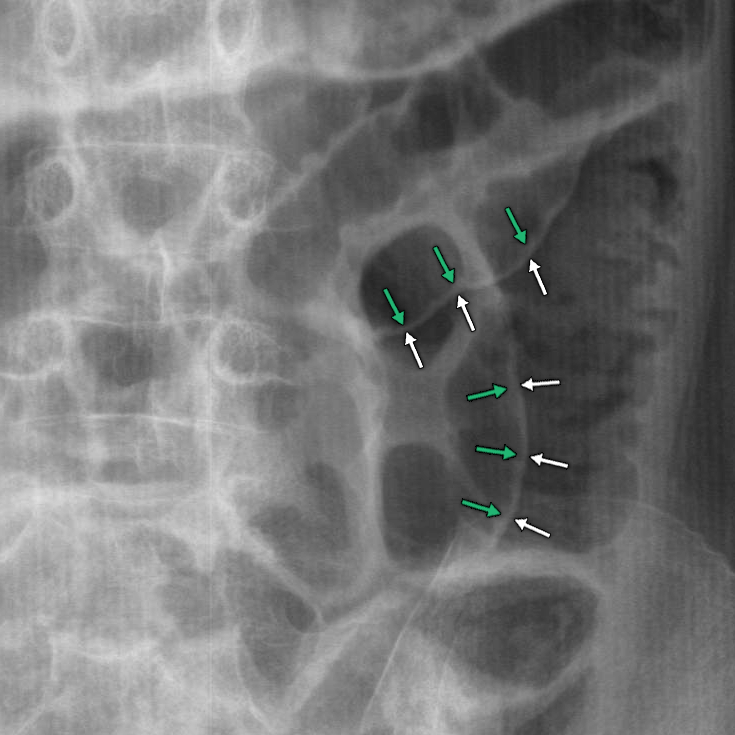

Rigler Sign (Double Bowel Wall Sign)

• Free gas/air is seen on both sides of the bowel causing the bowel wall to be very pronounced

• Indicates the presence of pneumoperitoneum